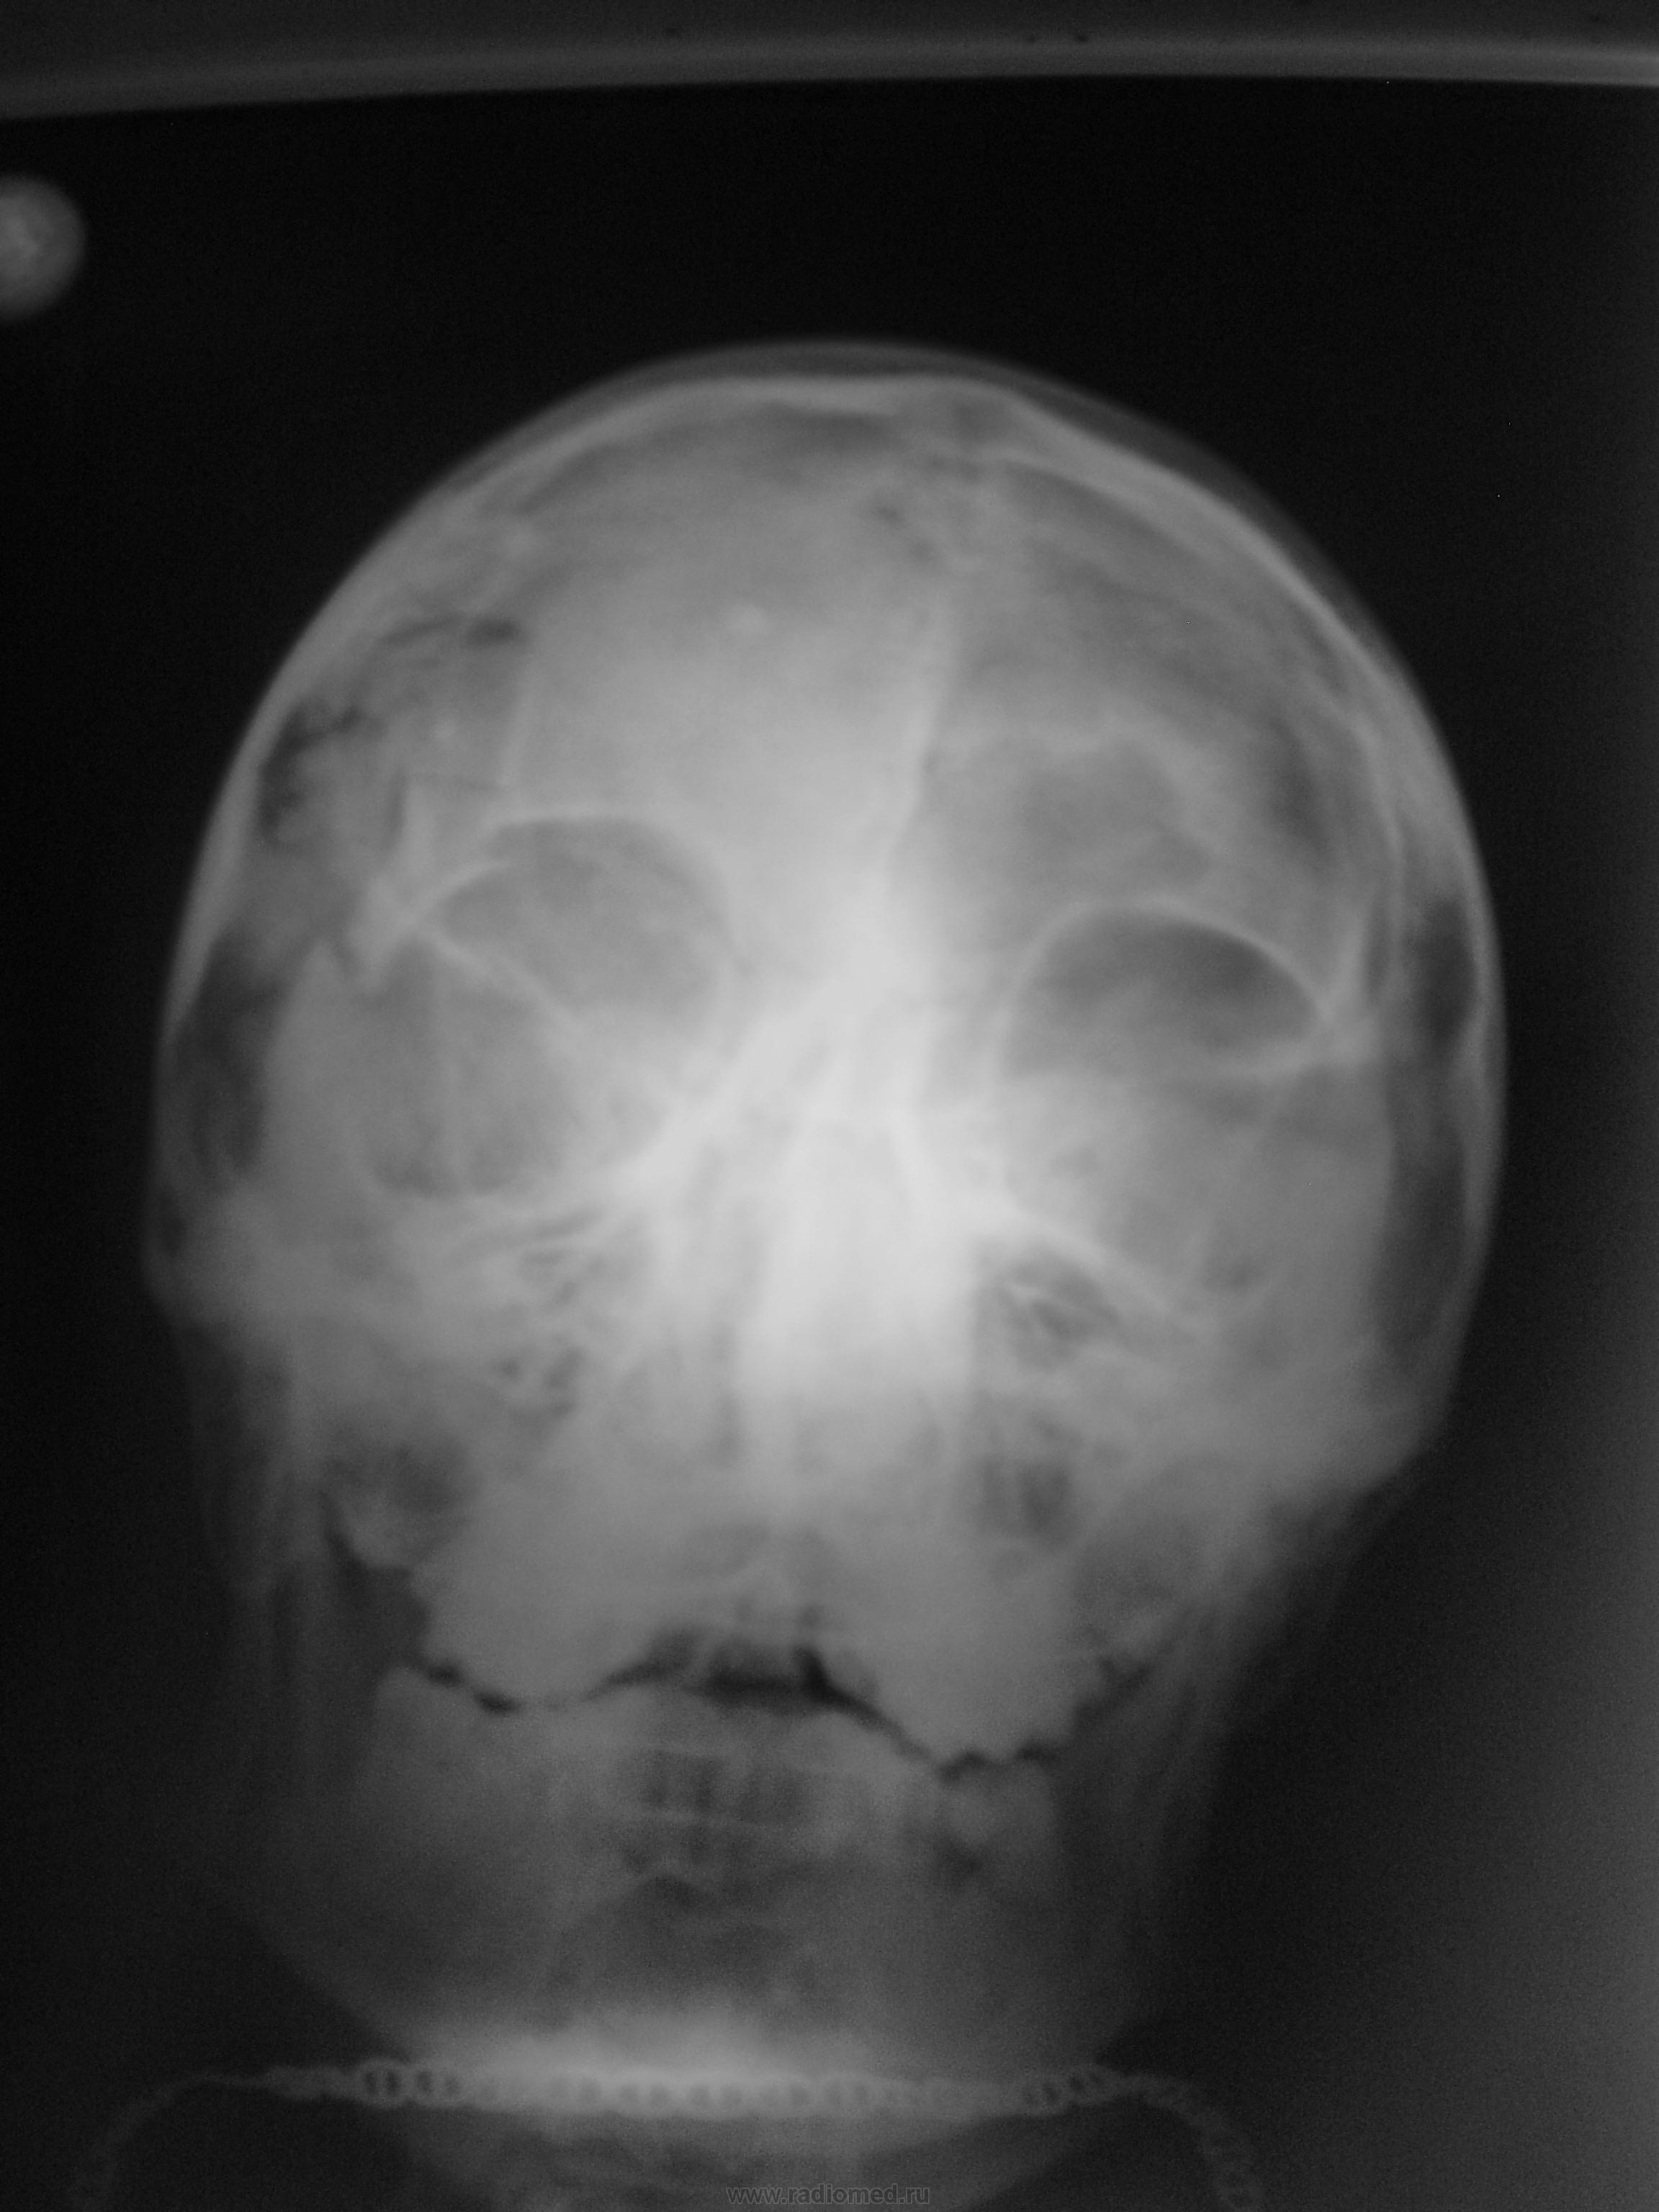

Травма. Пациент без сознания. Снимки сделаны передвижным аппаратом.

Фрагменты с увеличением.

Сильны удар в левую височную область. Перелом вис. кости, наружного края левой глазницы. Но вот что в полости черепа? Осколок кости или резиновой пули пули?

Было ДТП, стрельбы на было, был сбит бетонный столб...

Я вижу перелом верхнего края правой орбиты, т.е. перелом лобной кости с переходом на дно передней черепной ямки, травматическое расхождение лобно-скулового шва (извините, если неправильно назвала шов, забыла, но вы поняли о чем речь). Не исключается и перелом височной кости при такой травме.

Согласен, оскольчатый перелом лобной кости по верхней стенке орбиты, переход на лобно-скуловой шов с травматическим расхождением, большое крыло клиновидной кости возможно тоже вовлечено в височной ямке, с переломом наружной стенки правой орбиты, с переходом на переднюю часть чешуи височной кости.

Перелом чешуи височной кости и лобной кости с переходом на переднюю черепную ямку. Перелом основания скулового отростка лобной кости справа с повреждением наружной стенки правой орбиты со смещением, расхождение лобно - скулового сочленения. Дополнительно, наверное, есть перелом тела правой скуловой кости с переходом на нижнюю стенку глазницы.

Добавлю разрыв скуло-верхнечелюстного шва, гемосинус в правой гайморовой. Осколок столба вряд ли, компакт-осколок.